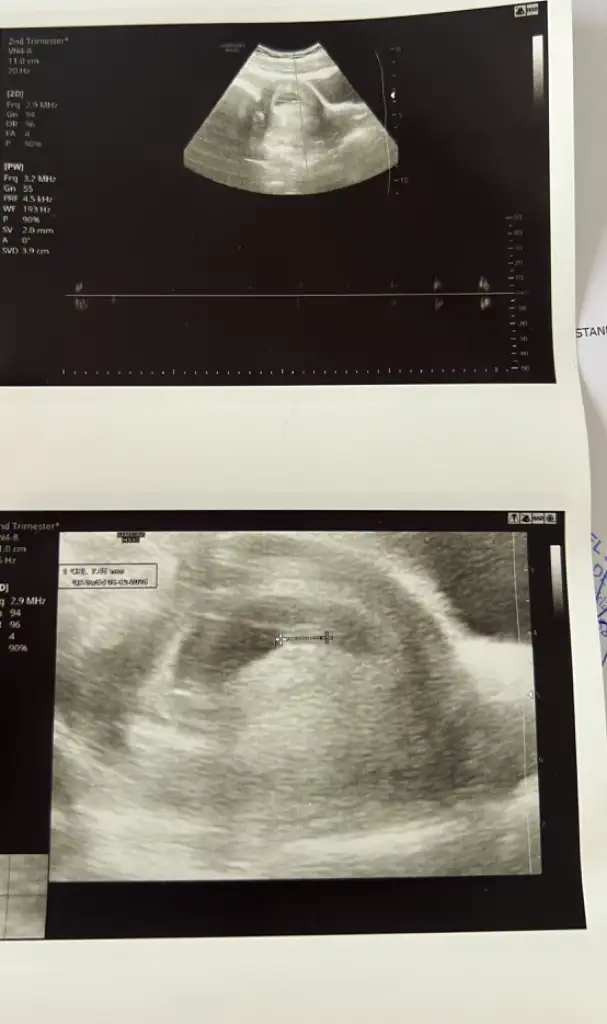

ay benimkini de yorumlar mısınız 🙏🏻 karından ultrason

• IMG_0283.webp

IMG_0283.webp

20,1 KB · Görüntüleme: 77

• IMG_0281.webp

IMG_0281.webp

23,9 KB · Görüntüleme: 59

Bu bebiş büyümüş tahmin etmek zor ☺️ ama içimden erkek geçti 🌸

Teşekkür ederim tahmininiz için elimde 6 hafta 4 günlük ultrason görüntüsüde var bebeğimin onada bakıp tekrar tahmininizi söyler misiniz rica etsem

• IMG_1912.webp

IMG_1912.webp

29,3 KB · Görüntüleme: 62